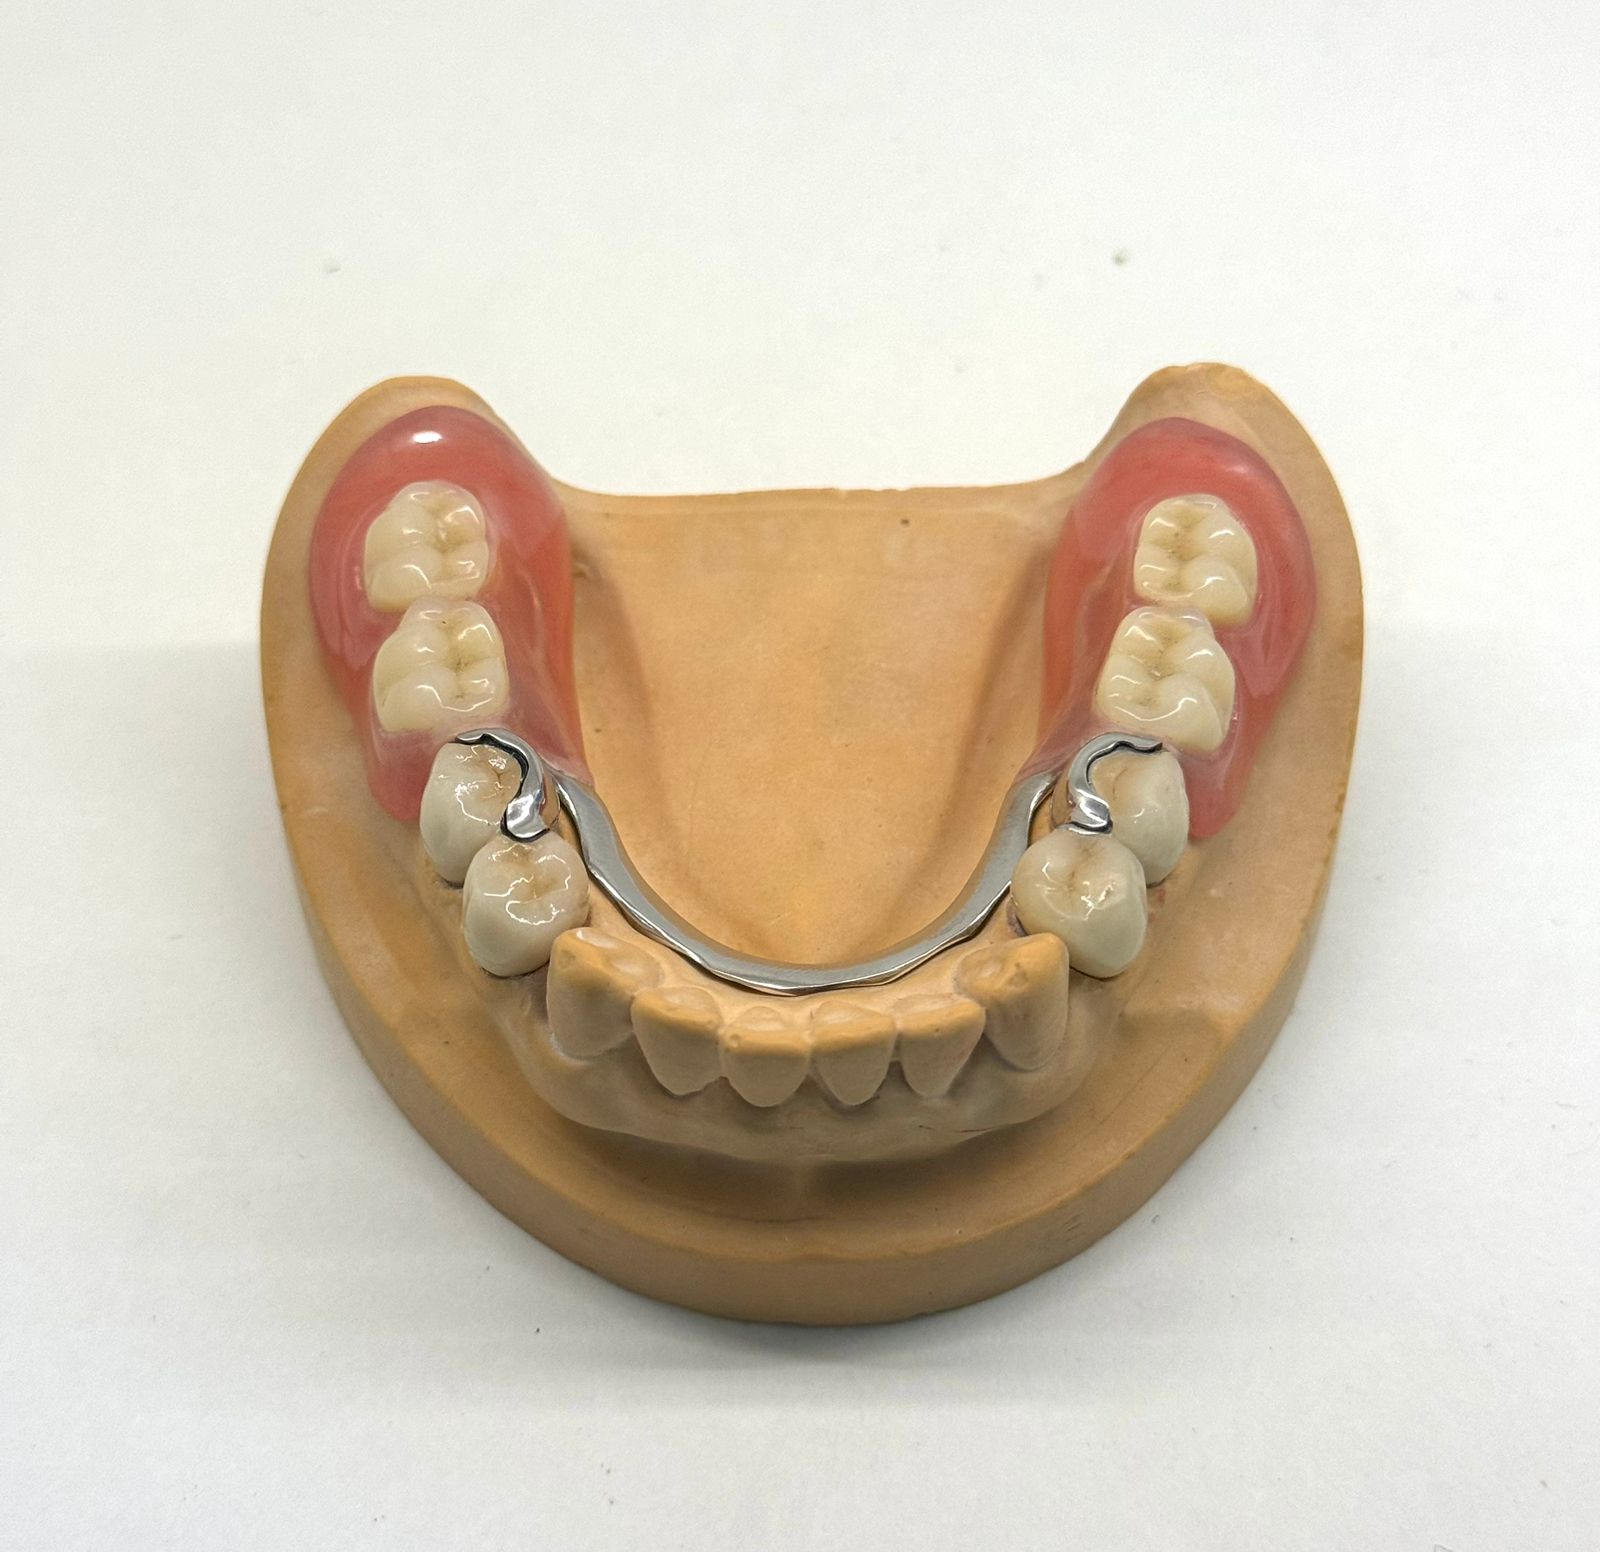

Примеры съемных зубных протезов в Хуньчуне

Съемные зубные протезы в Хуньчуне: виды, материалы изготовления, особенности выбора

Кому подходит: при полном или частичном отсутствии зубов. Подходит также пациентам с выраженной атрофией костной ткани, когда имплантация затруднена или временно не планируется.

Противопоказания: при наличии аллергии на металл используются конструкции без металлического каркаса — из современных гипоаллергенных материалов.

Сроки: изготовление и установка занимают 2–4 дня.

Гарантия: от 3 до 10 лет (у разных клиник).Стоимость от 25 000 рублей зависит от модели.